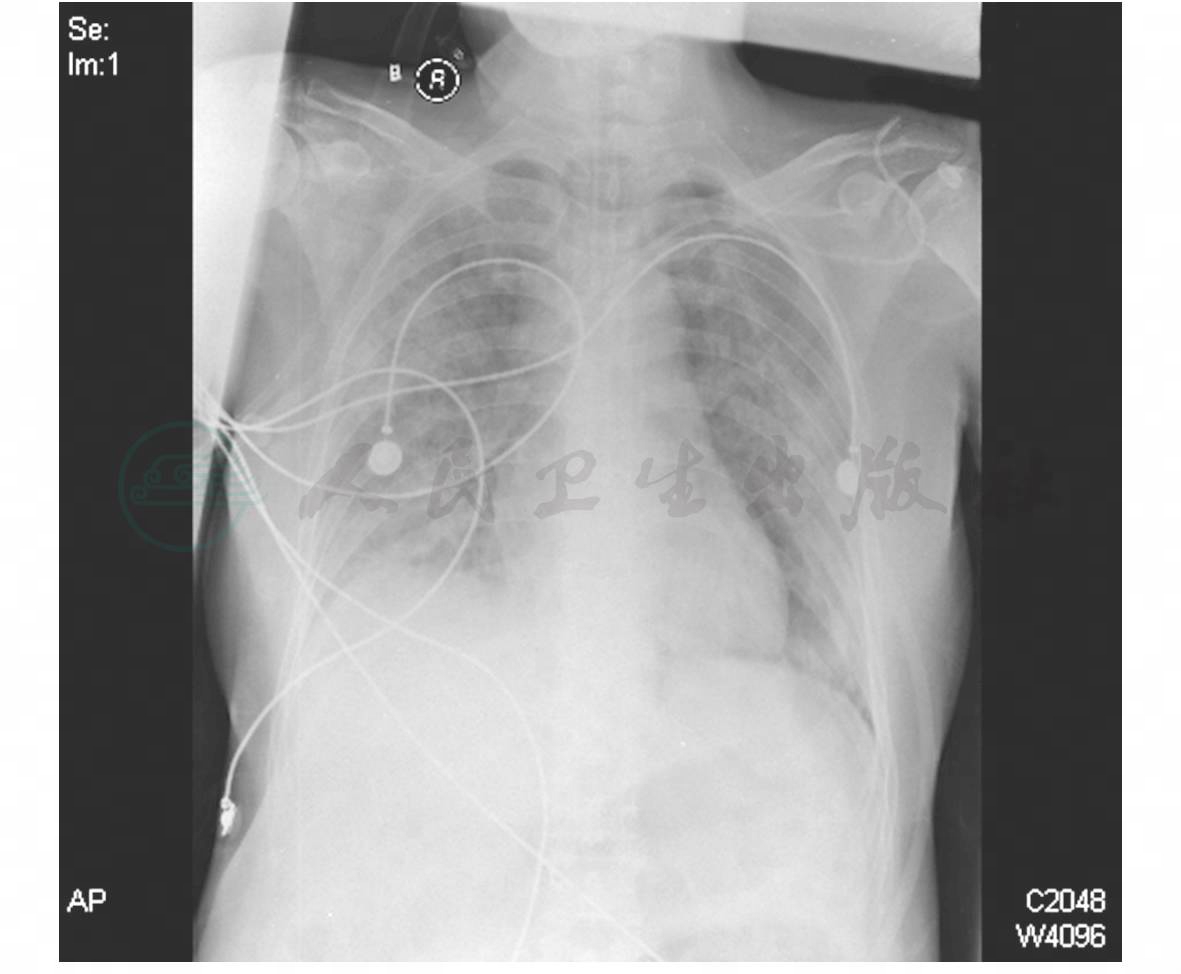

入院查体:T 37℃,P 130次/分,呼吸机辅助通气,BP 166/80mmHg[多巴胺10μg/(kg·min)]。平卧位,镇静状态。左手背肿胀明显,皮温高,可见一长约2cm切开口,按压有脓液溢出。经鼻气管插管,双肺可闻及散在湿性啰音,双下肺明显。血常规:WBC 13.9×109/L, N 86%,Hb 108g/L,PLT 165×109/L;清蛋白(Alb)27g/L;C反应蛋白(CRP)263.20mg/L;AST 89U/L;乳酸脱氢酶(LDH)564U/L;碱性磷酸酶(ALP)147U/L;D-二聚体1.19mg/L;血气分析:PaO2 70mmHg,PaCO2 31mmHg,pH 7.46,SaO2 94.5%(机械通气FiO2 60%);床边胸片双肺大量渗出性病变(图1)。初步诊断:重症肺炎(类鼻疽伯克霍尔德菌感染?),急性呼吸窘迫综合征,左手背脓肿,脓毒血症,感染性休克,2型糖尿病。

图1 胸片(2009-9-4):双肺大量渗出性病变